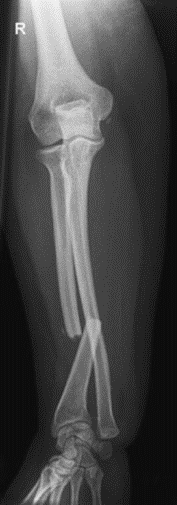

Na radiogramie uwidoczniono złamanie

A. nasady dalszej kości promieniowej.

B. trzonu kości łokciowej.

C. trzonu kości promieniowej.

D. nasady dalszej kości łokciowej.